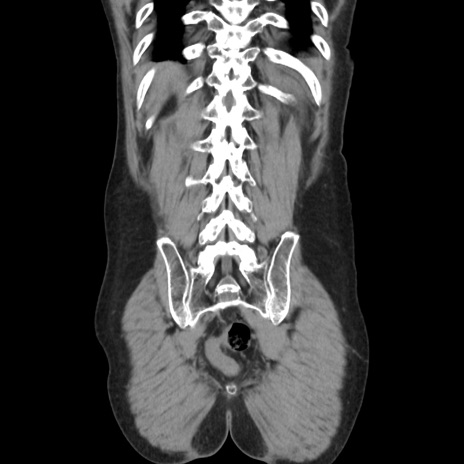

症例37(冠状断像)

【症例】40歳代 男性

【主訴】腹痛

【現病歴】4時間ほど前に電車に乗車中に臍部上より腹痛出現。徐々に増悪し起立困難となり、救急外来受診。生ものは数日食べていない。今朝お雑煮を食べた。

【身体所見】BT 36.8℃、BP 117/84mmHg、HR 91/min、SpO2 97%、苦悶様、腹部:臍上部広範囲圧痛あり、反跳痛±

【データ】WBC 8100、CRP 0.03